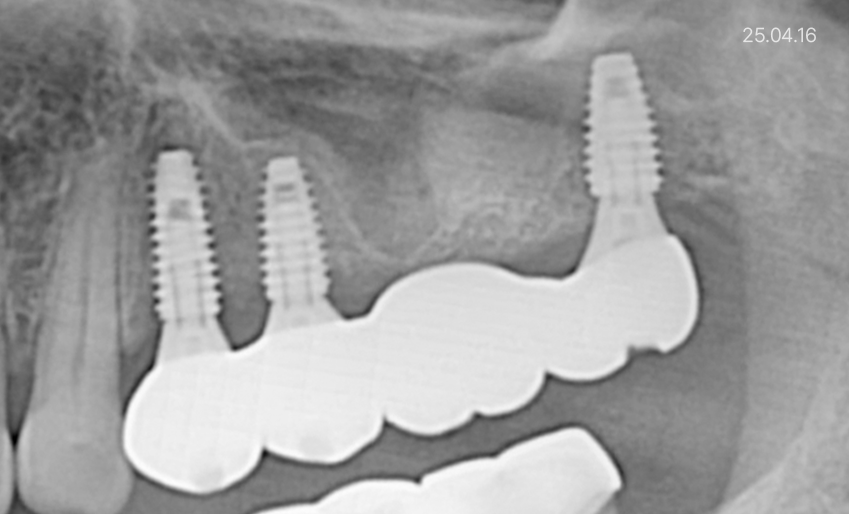

본 칼럼의 이해를 돕기 위해 본원에서 진료한 X-ray 사진을 동의 후 게시하였습니다. 진료 결과는 개인에 따라 붓기, 출혈, 통증이 생길 수 있어 주치의와 충분히 의논한 후 결정하시기 바랍니다.

임플란트 예시사진 25.04.16